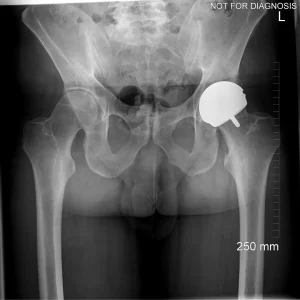

Hip resurfacing is a type of hip surgery used to treat hip arthritis, most commonly in younger and more active patients. Unlike a total hip replacement, hip resurfacing preserves more of your natural thigh bone. Instead of removing the entire femoral head (ball at the top of the thigh bone), the damaged surface is trimmed and covered with a smooth metal cap. The hip’s socket on the pelvis is also fitted with a metal cup.

Hip Resurfacing

- Preserves more natural bone (the femoral head is capped rather than replaced)

- Uses a larger ball size, which may reduce the risk of dislocation

- If needed, it can usually be revised to a total hip replacement